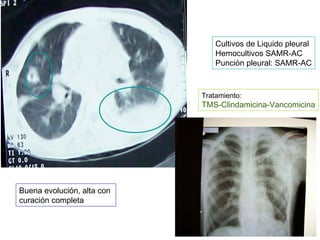

Cultivos de Liquido pleural

Hemocultivos SAMR-AC

Punción pleural: SAMR-AC

Tratamiento:

TMS-Clindamicina-Vancomicina

Buena evolución, alta con

curación completa